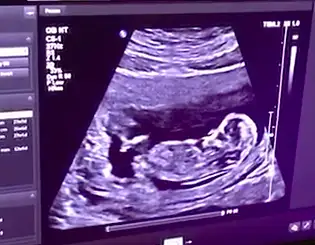

Buda benim bebişim 12 haftalık cinsiyeti sizce nedir😊

45CFB82A-2675-4DCE-89D8-BF5501063824.webp